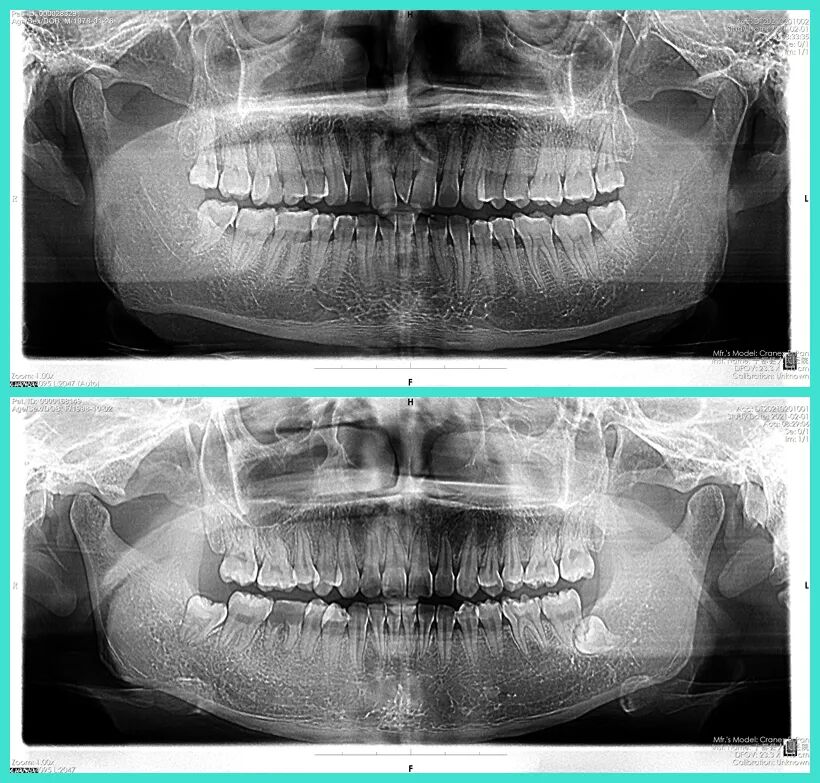

数字化全景牙科X线机

数字化口腔全景片